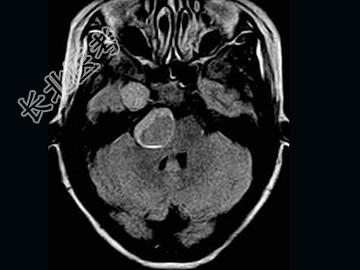

- 单项选择题女,41岁, 头痛,头晕, 走路不稳1个月余,MRI检查, 最可能的诊断为 ( )

A、听神经瘤

B、脑膜瘤

C、三叉神经瘤

D、胆脂瘤

E、神经纤维瘤